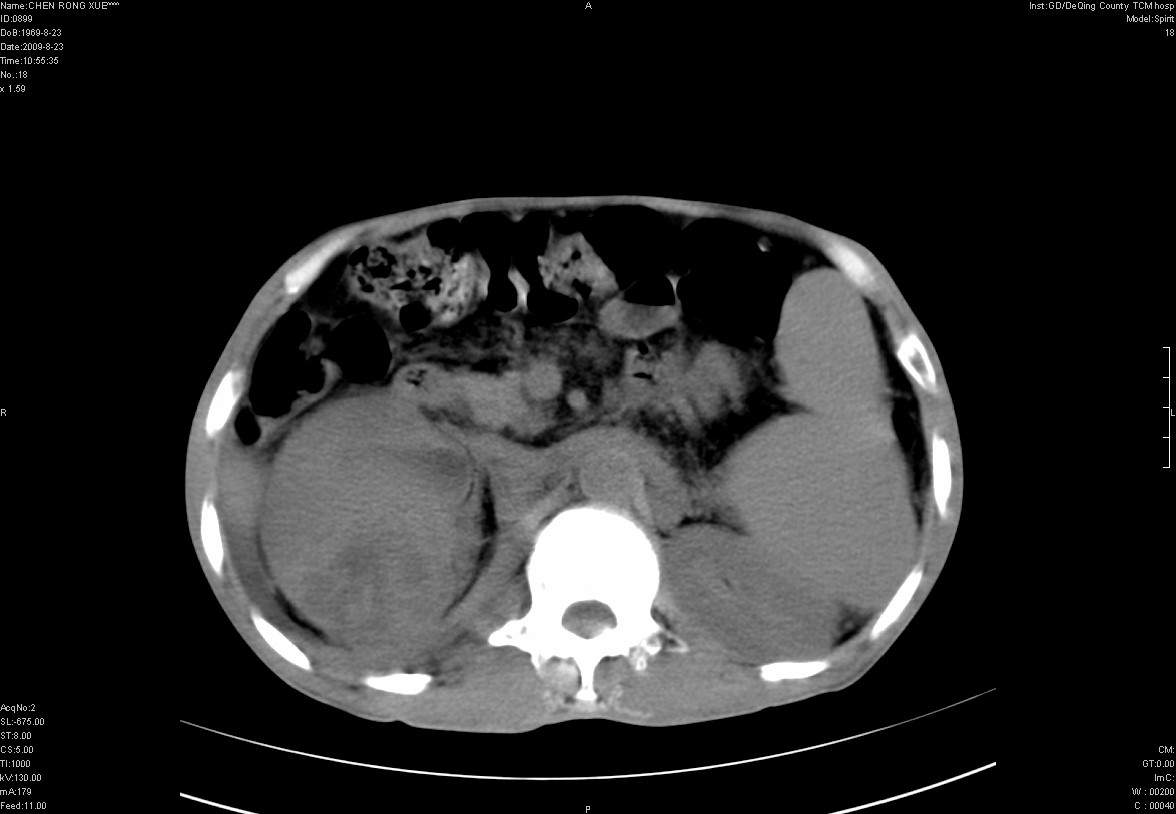

以下是引用zxl51642在2009-8-23 12:56:00的发言:[br]1、肝硬化、脾大;2、慢性胆囊炎;3、右肾占位并右侧腰大肌受侵,考虑恶性可能性大,建议增强扫描进一步检查。

以下是引用qiuleiyu在2009-8-23 15:17:00的发言:[br]1、慢性肝病,肝硬化,脾大,门脉高压。胆囊小结石。[br]2、右肾明显肿大,伴片状低密度灶,累及右侧腰大肌,肿瘤及炎症性病变皆有可能大,建议增强。

以下是引用zjzjr在2009-8-23 17:42:00的发言:[br]1、慢性肝病,肝硬化,脾大,门脉高压。胆囊小结石。[br]右肾脓肿波及肾周,建议增强

以下是引用dyqct在2009-8-23 16:53:00的发言:[br][quote]以下是引用qiuleiyu在2009-8-23 15:17:00的发言:[br]1、慢性肝病,肝硬化,脾大,门脉高压。胆囊小结石。[br]2、右肾明显肿大,伴片状低密度灶,累及右侧腰大肌,炎症性病变可能,建议增强。